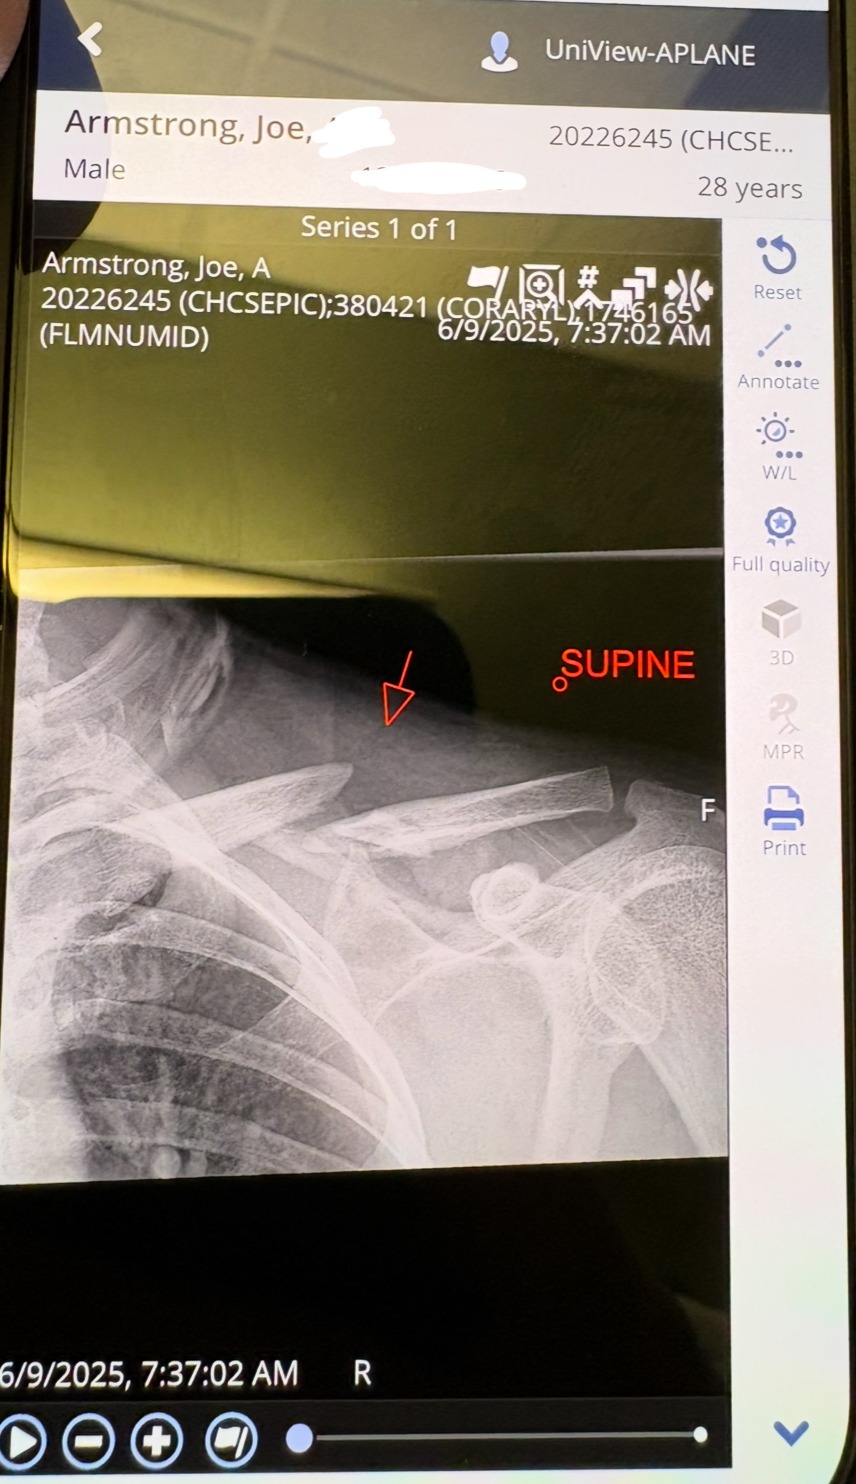

On Sunday, June 8th, 2025, Joe was in a devastating motorcycle accident. He sustained multiple serious injuries, including a broken back, neck, and collarbone. His clavicle suffered an open fracture at the midshaft, along with fractures to the superior articulating transverse processes in C7, the spinous processes in T3 and T4, and compression fractures from T6 to T9.